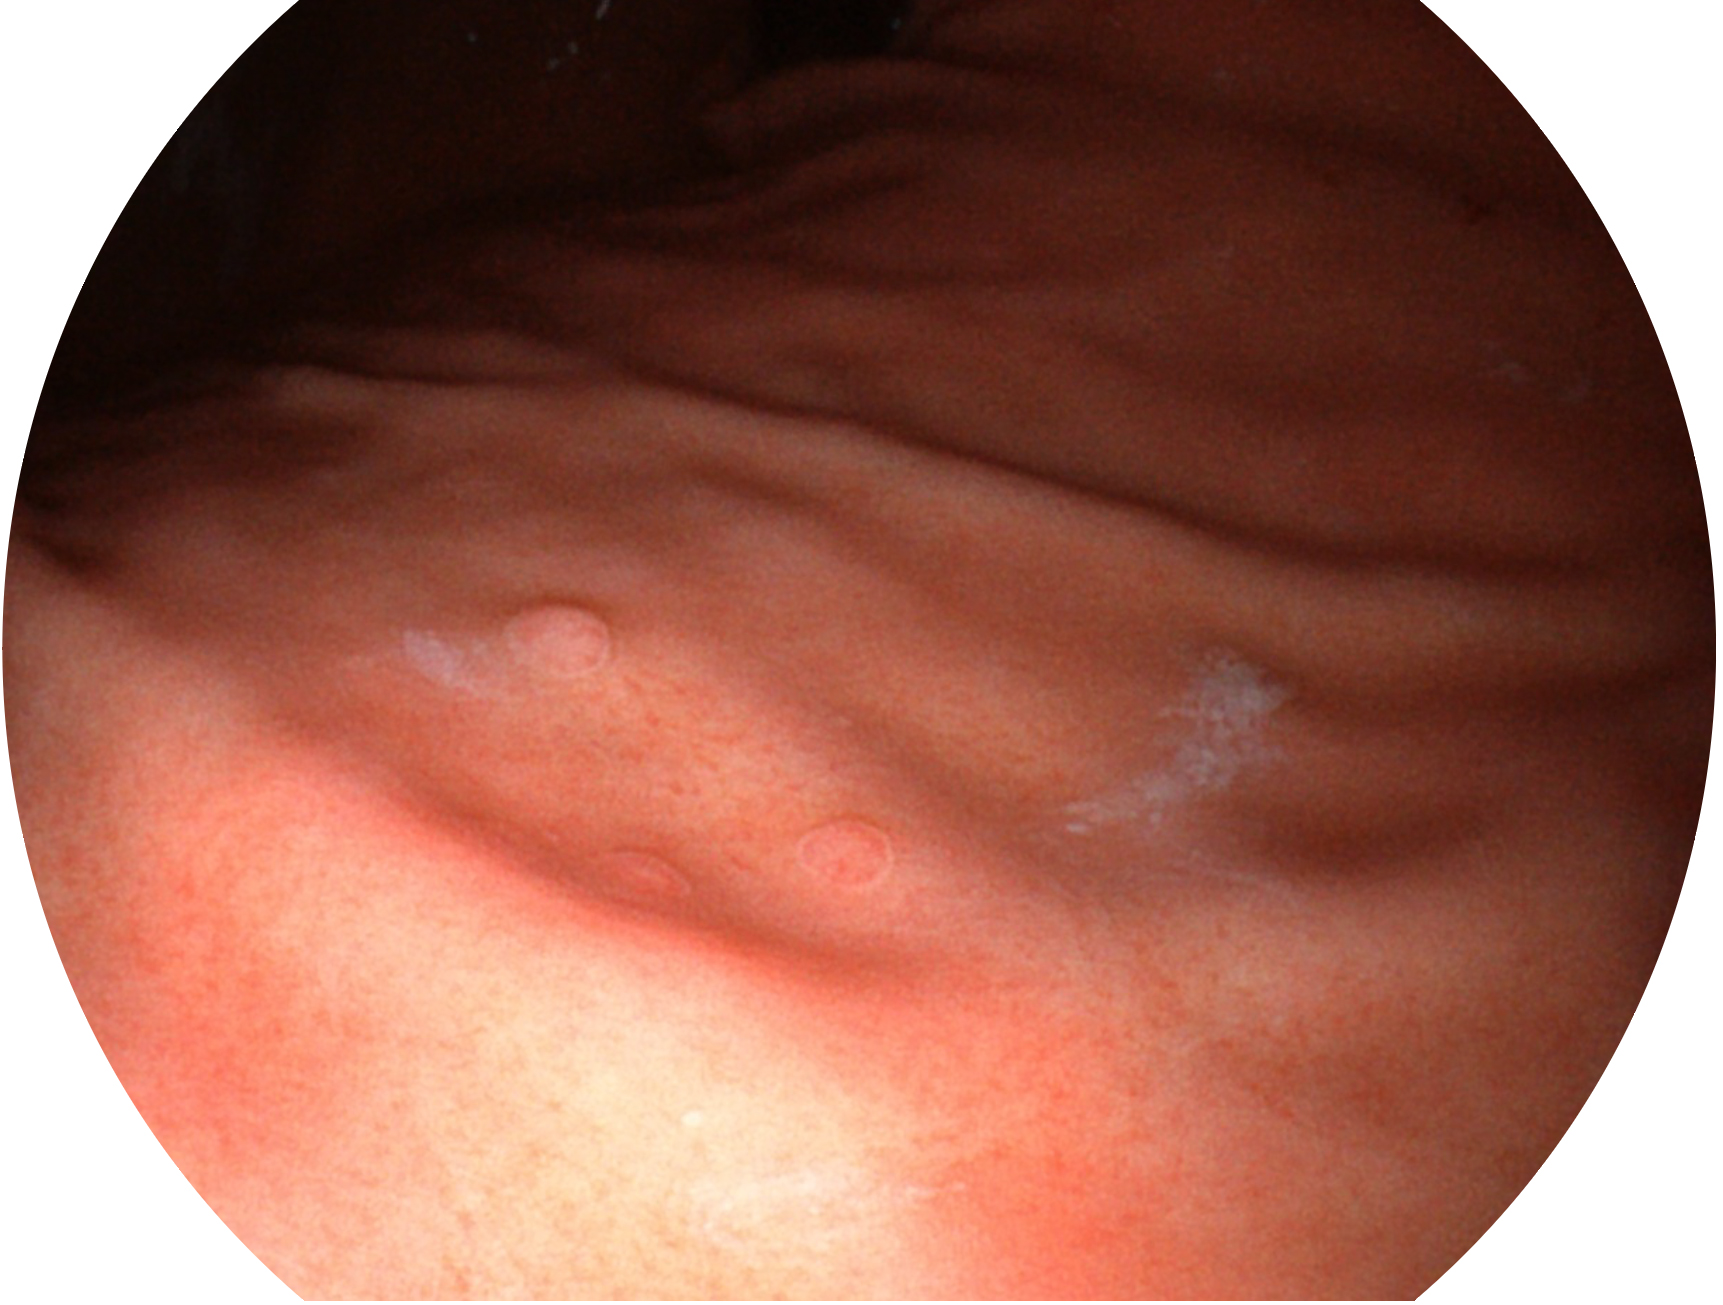

球速体育入口新开发的内镜染色技术,主要是基于多波长LED 光源的开发,VLS-55Q 四波长LED 光源是由四个不同颜色的LED光按照相应照明模式所规定的特定发光比例进行合束后形成,合束后形成的照明光的光谱由红光、绿光、蓝光及蓝紫光这四个不同的波段范围构成。具有更高光谱自由度,通过光谱比例的控制,实现了聚谱成像技术,英文全称为“Spectral Focused Imaging, SFI”,缩写为“SFI”和光电复合染色成像技术,英文全称为“Versatile Intelligent Staining Technology, VIST”,缩写为“VIST”。